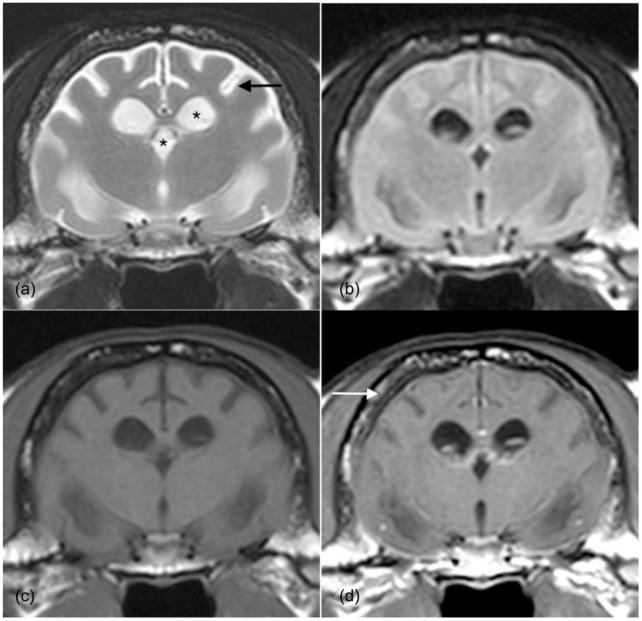

A 2-year-old male domestic shorthair cat presented to the University of Liverpool Small Animal Teaching Hospital with a 2 week history of altered mentation, blindness and focal epileptic seizures. MRI examination revealed generalised cerebral and cerebellar atrophy, diffuse T2-weighted hyperintensity of the white matter and meningeal thickening. Neuronal ceroid lipofuscinosis was confirmed on post-mortem examination.

一只2岁的雄性家猫被送到利物浦大学小动物教学医院,有2周精神状态改变、失明和局灶性癫痫发作的病史。MRI检查显示大脑和小脑普遍萎缩,白质在T2加权像上呈弥漫性高信号,脑膜增厚。尸检确诊为神经元蜡样脂褐质沉积症。